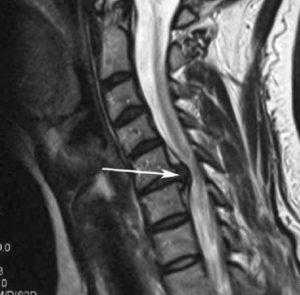

Стеноз шейного отдела вследствие грыжевого выпячивания.

Межпозвонковая грыжа представляет собой смещение или выпадение фрагментов диска (пульпозного ядра или элемента окружающего его разорванного фиброзного кольца) в позвоночный канал. Компрессия нервных корешков и окончаний при этом вызывает боль и дискомфорт.